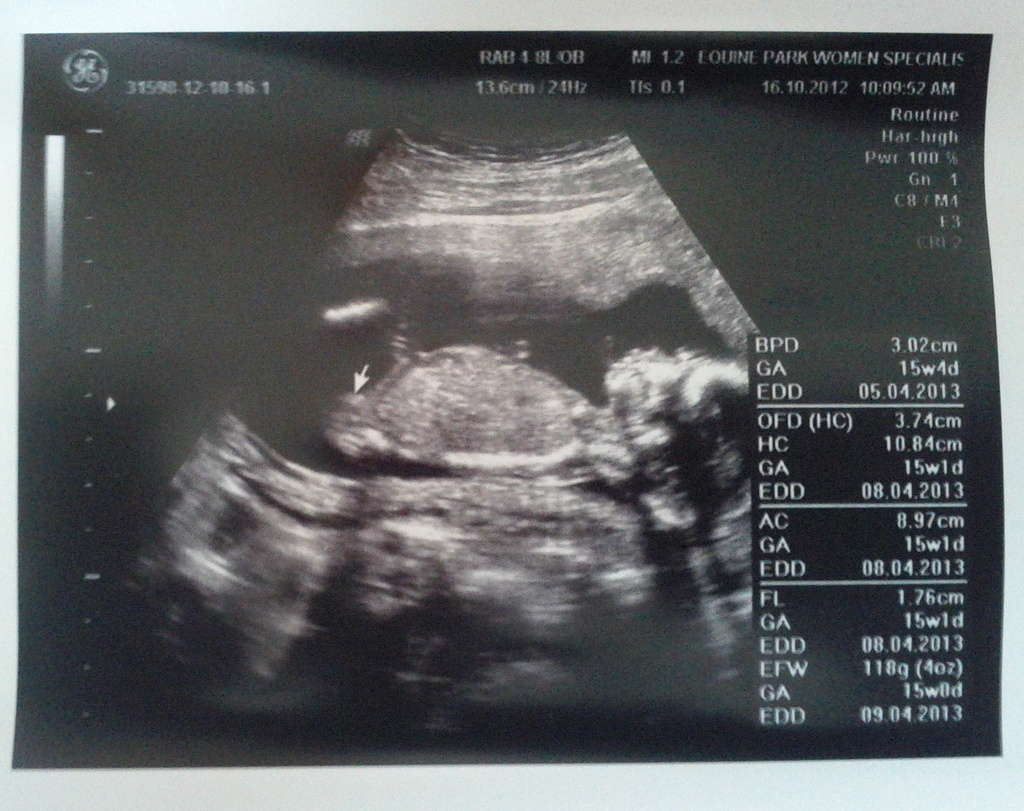

Such a relief to see you ...

First thing you showed us is your butt... how nice...

Then those little movements, aaahhh.... makes mommee so happy la...